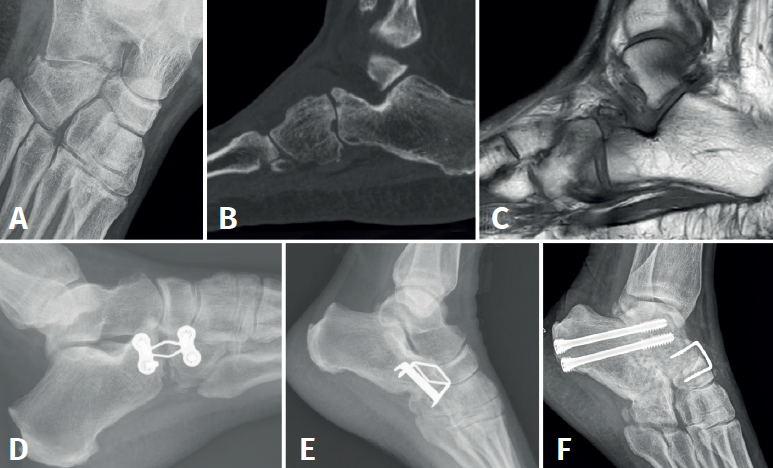

Los pacientes que no fueron detectados inicialmente tuvieron una puntuación media de 35 puntos (rango: 25-50). La diferencia entre ambas puntuaciones en la escala funcional fue estadísticamente significativa (p < 0,05). En cuanto a las 6 fracturas no detectadas inicialmente, 4 (66,7%) desarrollaron como complicación artrosis calcaneocuboidea durante el seguimiento clínico. Todos estos casos presentaban como lesión asociada la fractura de la pars anterior del calcáneo que puede conllevar un mayor grado de artrosis postraumática precoz. De los 4 casos con artrosis calcaneocuboidea, 3 (75%) precisaron de cirugía de secuelas mediante artrodesis calcaneocuboidea aislada. En los 3 casos se realizó la artrodesis mediante autoinjerto y placa a compresión con tornillos. Durante el seguimiento, 2 de estos 3 pacientes (66,7%) presentaron como complicación la ausencia de consolidación de la artrodesis, precisando ambos reartrodesis de la articulación calcaneocuboidea. Tras la segunda intervención quirúrgica y pese a la consolidación de la artrodesis calcaneocuboidea, los pacientes presentaban incapacidad funcional, dolor y afectación de las articulaciones vecinas (puntuación en la escala de la AOFAS < 50 puntos), por lo que se realizó cirugía reconstructiva de rescate en un caso mediante doble artrodesis (subastragalina y calcaneocuboidea) y, en el otro restante, mediante triple artrodesis (subastragalina, calcaneocuboidea y astragaloescafoidea) (Figura 4).

Diversos trabajos presentes en la literatura(12,13) evidencian pobres resultados clínico-funcionales, así como una elevada tasa de pseudoartrosis (hasta un 50%) tras la realización de artrodesis calcaneocuboidea como único gesto quirúrgico tras artrosis de la articulación. De la misma forma, en el estudio realizado por Barmada et al., los autores sostienen que la artrodesis por distracción calcaneocuboidea, que tiene como objetivo recuperar la longitud ósea a la vez que se fija la articulación entre el calcáneo y el cuboides, puede estar asociada con limitaciones funcionales y complicaciones como la pseudoartrosis (siendo esta la más frecuente), la consolidación defectuosa o la fractura por estrés de la columna lateral. De esta manera, la artrodesis calcaneocuboidea debería realizarse como un procedimiento complementario asociado a otros gestos quirúrgicos en el retropié, como la artrodesis de la articulación de Chopart, la doble artrodesis (artrodesis subastragalina y calcaneocuboidea) o la triple artrodesis (subastragalina, calcaneocuboidea y astragaloescafoidea)(11).

La alta tasa de complicaciones (66,6% de pseudoartrosis) y los pobres resultados clínicos obtenidos (escala AOFAS < 50 puntos) mediante la artrodesis calcaneocuboidea aislada, incluso consiguiendo la consolidación de dicha artrodesis, en los pacientes de nuestro estudio están en consonancia con los resultados funcionales publicados por Grunander(12) (50% de pseudoartrosis) y con las alteraciones biomecánicas descritas por Barmada(11) y Chen(13), por lo que consideramos que se debe ser cauto con la indicación de la artrodesis calcaneocuboidea como gesto quirúrgico aislado, abogando por el uso de otras técnicas reconstructivas como la doble o triple artrodesis del retropié de entrada.